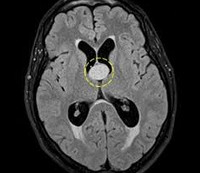

На снимках компьютерной томографии коллоидная киста выглядит круглым образованием белесого цвета, которое располагается в полости III желудочка мозга, имеющего на рентгенограмме черный цвет. Окраска ткани кисты намного интенсивнее соседней ткани головного мозга, которая имеет на снимках сероватый оттенок.